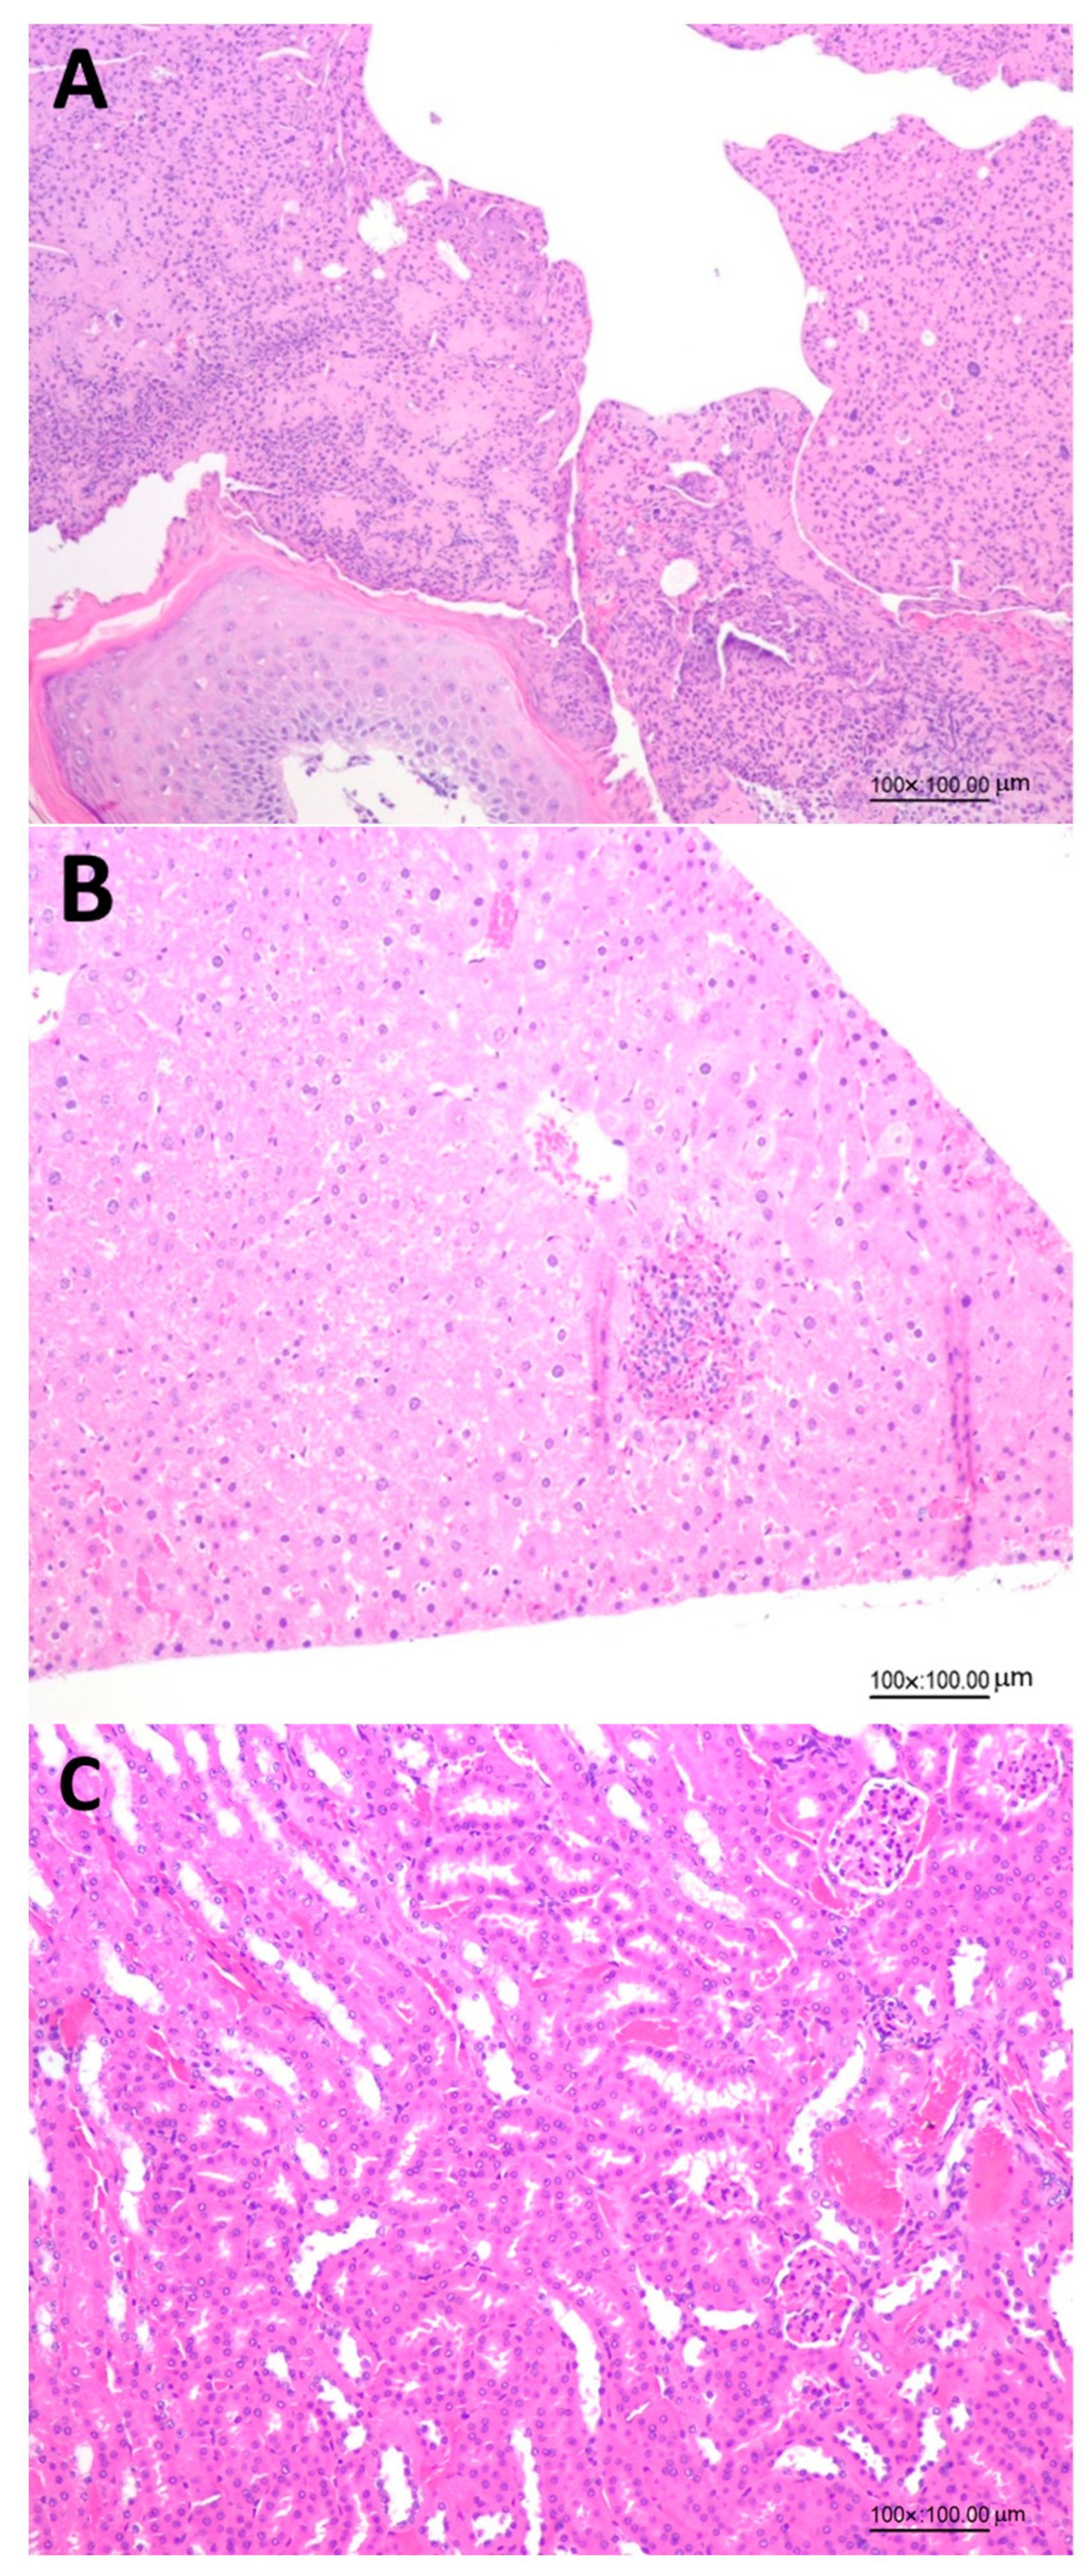

3.6. Pathological Analysis of Wounded Skin, Kidney and Liver of Mice